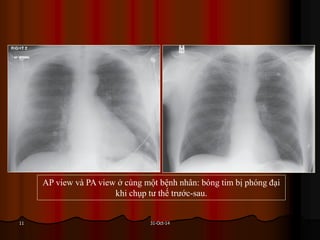

AP view và PA view ở cùng một bệnh nhân: bóng tim bị phóng đại

khi chụp tư thế trước-sau.

31-Oct-1411 AP view vàPA view ở cùng một bệnh nhân: bóng tim bị phóng đại khi chụp tư thế trước-sau.